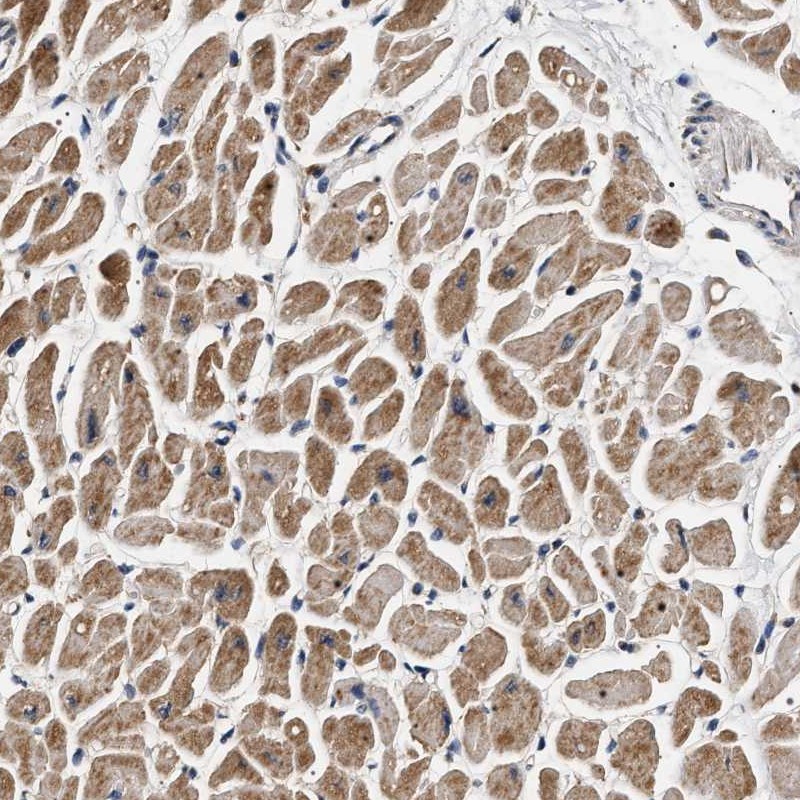

Immunohistochemical staining of human heart muscle shows moderate cytoplasmic positivity.